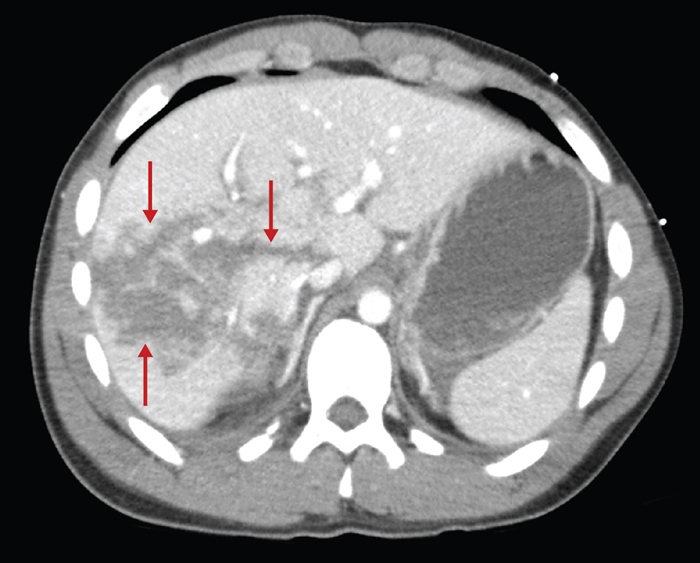

Duodenal and pancreatic injuries due to BAT are relatively uncommon but may present with nausea, vomiting, inability to tolerate oral intake, progressive abdominal pain, and sepsis. Patients with duodenal hematomas may also have evidence of small-bowel obstructions. However, neither duodenal hematomas nor pancreatic transections are commonly associated with free intraperitoneal fluid.

Duodenal hematomas (DHs) most commonly occur following blunt abdominal trauma (BAT). They are more commonly seen in children due to a number of anatomic differences, including thinner abdominal wall musculature, less abdominal adipose tissue, and more pliable ribs (which absorb less force than the stiffer ribs of adults). DH commonly occurs when a blunt force rapidly compresses the duodenum against the vertebral column. Following trauma, blood collects between the submucosal and muscular layers of the duodenum causing partial or complete obstruction.

Patients with DH due to BAT may initially have only symptoms of abdominal wall trauma, which may improve before subsequent clinical deterioration as the DH expands. Patients classically present 24-36 hours after the initial event with epigastric pain and vomiting due to failure to pass gastric contents beyond the obstructing hematoma. Diagnosis is confirmed with CT imaging of the abdomen.

Most DHs will resolve in 1-2 weeks. Management involves decompression by nasogastric tube and, in many patients, parenteral nutrition. Surgery or percutaneous drainage may be considered to evacuate the hematoma if nonoperative management fails.